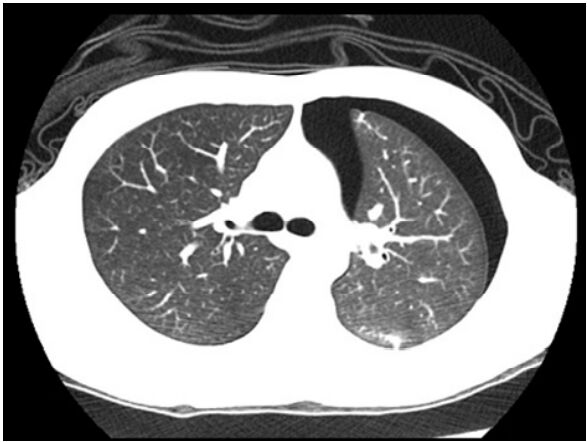

38.男性患者突然左胸痛,未施打顯影劑的胸腔電腦斷層在左肺旁發現異常(如下圖所示),最適當的診斷為 何?

(A)氣胸(pneumothorax) (B)血胸(hemothorax) (C)乳糜胸(chylothorax) (D)連枷胸(flail chest)